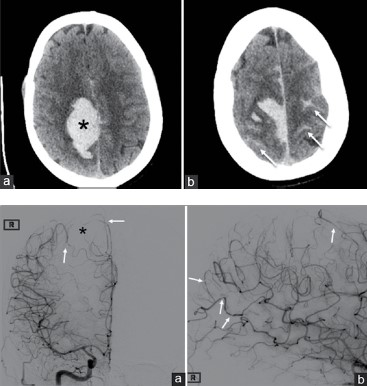

Paciente do gênero feminino, de 35 anos de idade, 10 dias após o parto, procura o serviço de neurologia com quadro de cefaleia occipital, de forte intensidade, que se iniciou 2 dias antes da consulta; apresenta também moderada confusão mental, náuseas, vômitos e dificuldade de deambulação. Ao exame neurológico, paciente normotensa, ritmo cardíaco normal e se constata hemiparesia e hemihipoestesia esquerda. Exames de neuroimagem são apresentados a seguir.

Considerando esses elementos, qual seria a sua primeira hipótese diagnóstica?